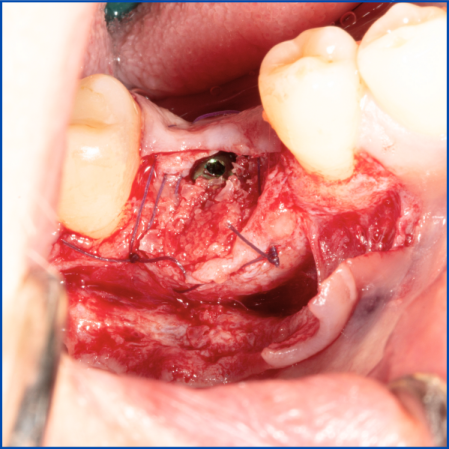

Kist nedeni ile çene kemiğinde defekt oluşmuş vakamıza sert ve yumuşak doku ogmentasyonu uyguladık